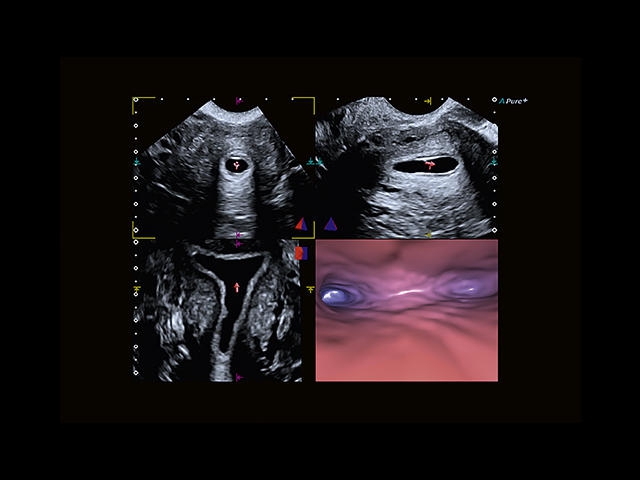

• Fly Thru. Виртуальная эндосонография обеспечивает построение трехмерной модели полостей, протоков и сосудов в рельном времени, облегчает организацию инвазивных процедур и динамических исследований. Посредством Fly Thru можно установить шунты и стенты, проводить точные оперативные вмешательства.